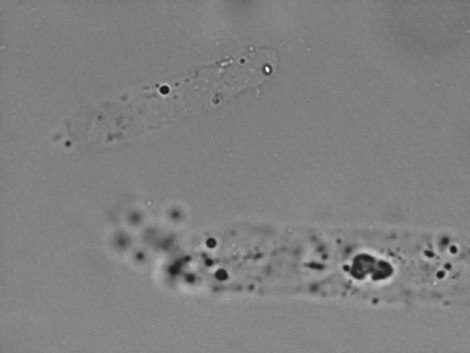

Ejemplos de imágenes

Hasta 96 imágenes están incluidas con cada ejecución de la muestra, con 6 imágenes automáticamente seleccionadas para su revisión. O elija y seleccione cuáles imágenes resaltar: todas se guardan en la base de datos con un solo clic.

Todas las imágenes son representativas de un campo de visión con objetivo de 40x. Las imágenes se toman del VETSCAN SA.

Cilindros hialinos